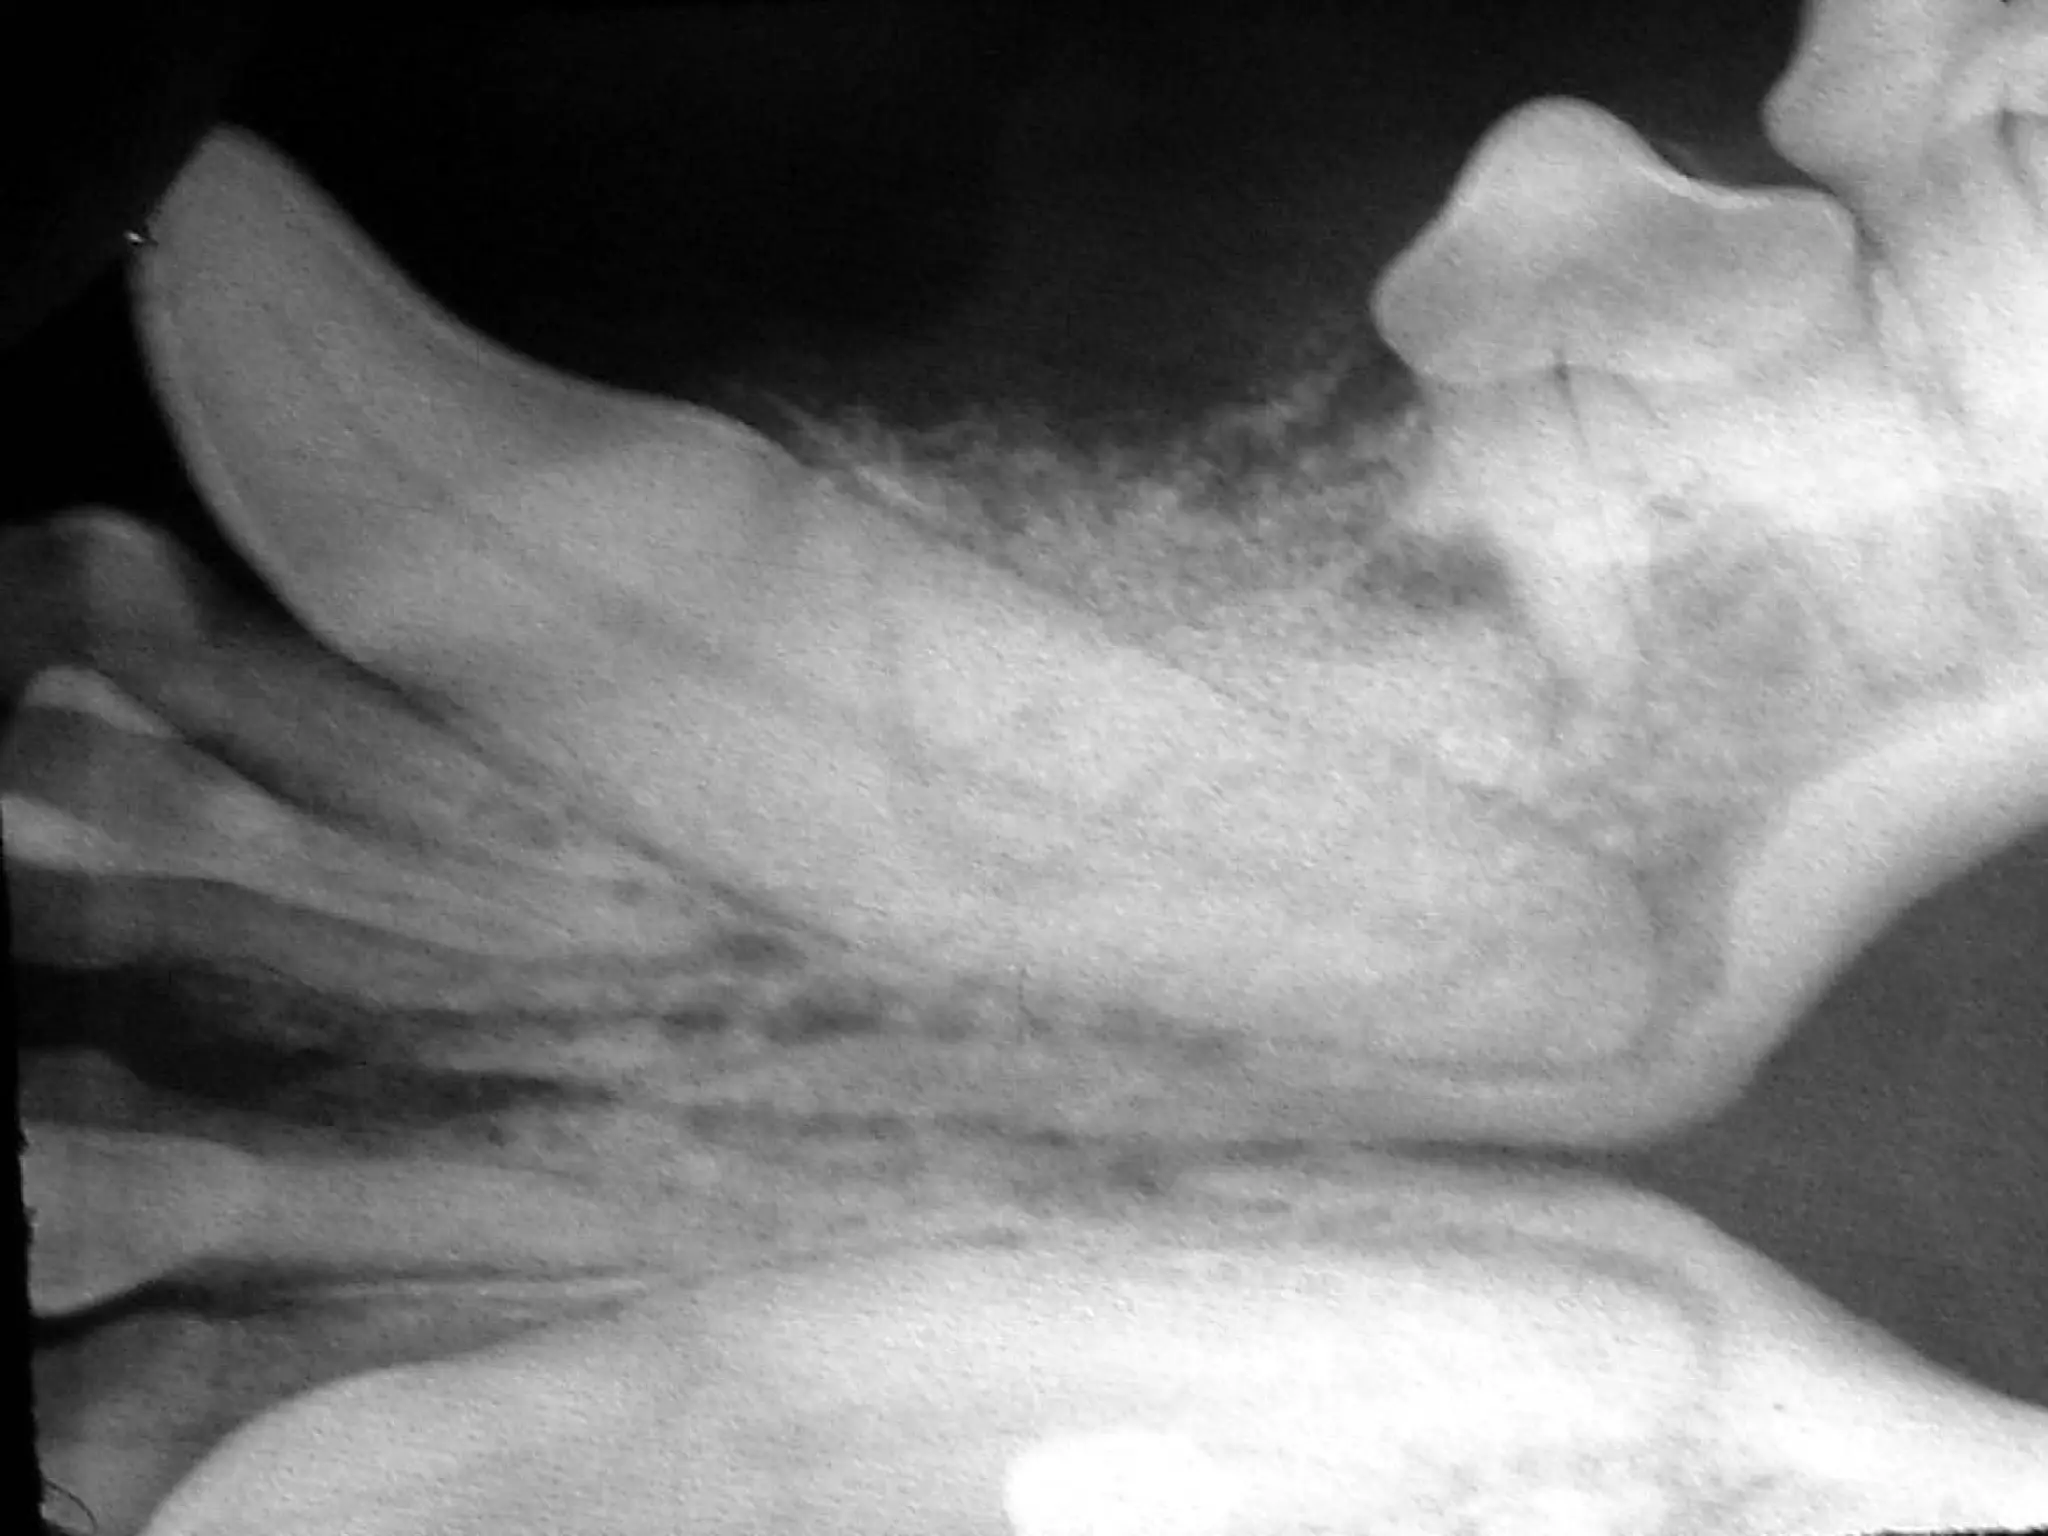

• #7 August 04

• #34 ROSTRAL MANDIBULAR (MENTAL) REGIONAL BLOCK The rostral mandibular block infiltrates the rostral extent of the inferior alveolar nerve just before it exits the middle mental foramen. (Figures 6 and 7) The structures anesthetized include the incisors, the canine and the first three premolars. The adjacent bone and soft tissue are also affected. The middle mental foramen is located about 1/3 of the distance from the ventral border to the dorsal border of the mandible at the level of the mesial root of the second premolar. The landmark for infiltration is the mandibular labial frenulum. The frenulum is retracted ventrally. The needle is inserted at the rostral aspect of the frenulum and advanced along the mandibular bone to just enter the canal. If bone is encountered the needle should be backed out and redirected until the needle passes freely into the foramen. Placement can be confirmed by moving the syringe laterally to encounter the lateral aspect of the canal. The patient’s jaw, rather than the alveolar mucosa, will move slightly if the needle is within the canal. The mental nerve block gets the mandibular bone, teeth and soft tissue from the second premolar to the midline. The mandibular labial frenulum is retracted ventrally. The needle is directed into the mesial aspect of the frenulum and advanced against the bone distally to enter the middle mental foramen at the level of the distal frenulum.